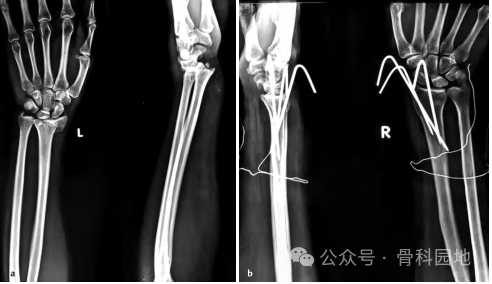

5、对于严重骨质疏松症,最好使用四到五根克氏针来固定骨折处。有时为了保持桡骨的长度,使用横向克氏针将桡骨远端骨块固定到尺骨远端。

6、在干骺端长节段骨折中,可以使用大倾斜的克氏针固定。但克氏针可能会滑入髓腔很难固定(下图a-d)。

8、桡骨远端严重粉碎性骨折伴缩短和塌陷,需额外的横向克氏针穿过尺骨,以保持桡骨的高度,该克氏针最好从茎突的掌侧指向尺骨背侧方向,如下图a、b 所示。